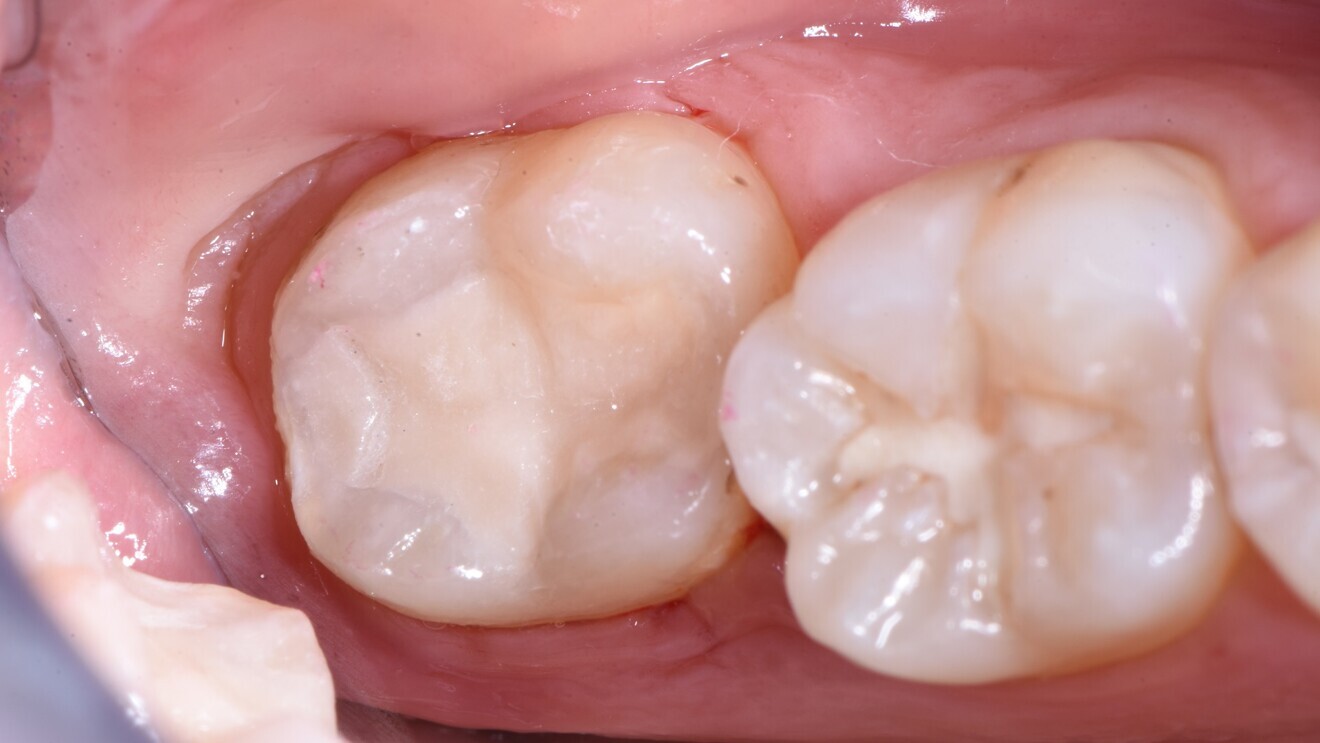

Fig. 3: Glass hybrid restorations at follow-up after 6.5 years.

In summary, both studies—randomised trials of a robust design—indicate the suitability of glass hybrids for restoring cervical lesions. Moreover, they not only demonstrate that the material shows similar survival, but also flag the advantageous cost-effectiveness of this material. That glass ionomer materials work well for this indication is not necessarily new. However, aspects concerning the economic differences between composites and glass hybrids for managing cervical lesions had not been assessed in detail before. Regardless of the restorative material used, preparation of sclerotic surfaces is likely beneficial.